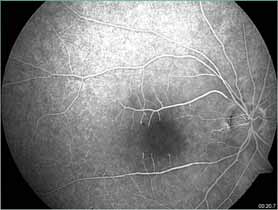

duration. The patient also had cerebral infarction. The vision ��� ���� ��������� ���� ���� ������ ��������� ������ ��� ������ ������������ ��� ���� ����������� ���� ������� ������ ���� ����� ������������� �������������� �������� ���� ������������ ������������showed pruning of the macular vessels in the perifoveal region. (Figure 3b)